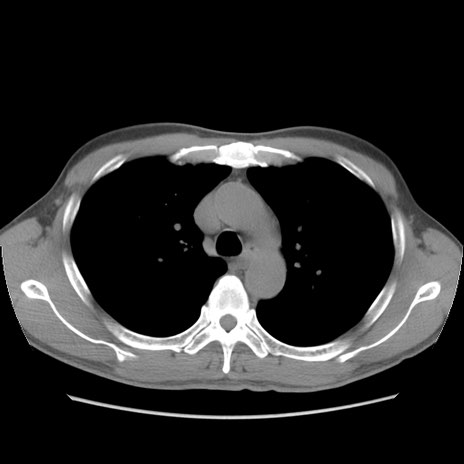

症例56 CT(横断像)

脂肪ウインドウ